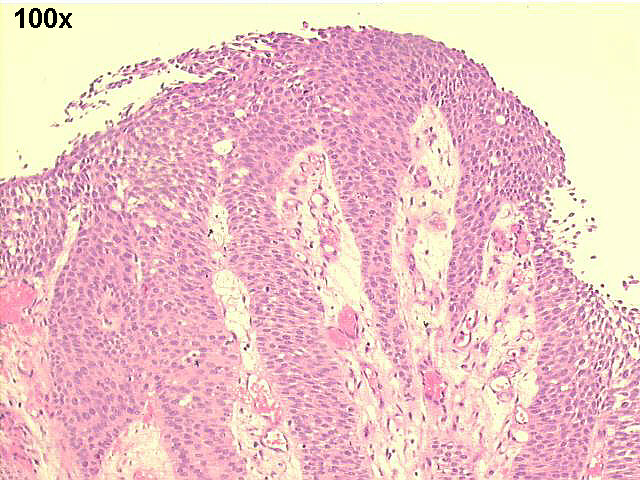

100x H&E staining, showing papillary urothelial carcinoma grade II~III

The cytological smears showed many fragments of papillary structures, with moderate cellular atypias, suggesting urothelial papillary carcinoma. Cystoscopic biopsy confirmed this diagnosis. The surgical specimen revealed a papillary urothelial carcinoma grade II~III (high grade urothelial carcinoma ISUP), with some areas of necrosis, stage T2 (penetration of muscularis).